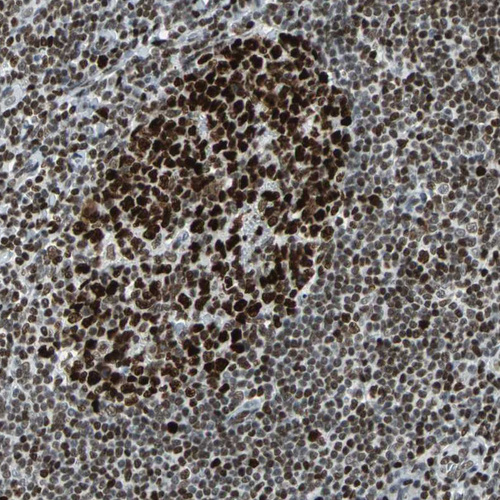

Immunohistochemical staining of human tonsil tissue shows strong nuclear positivity in non-germinal center cells and germinal center cells.